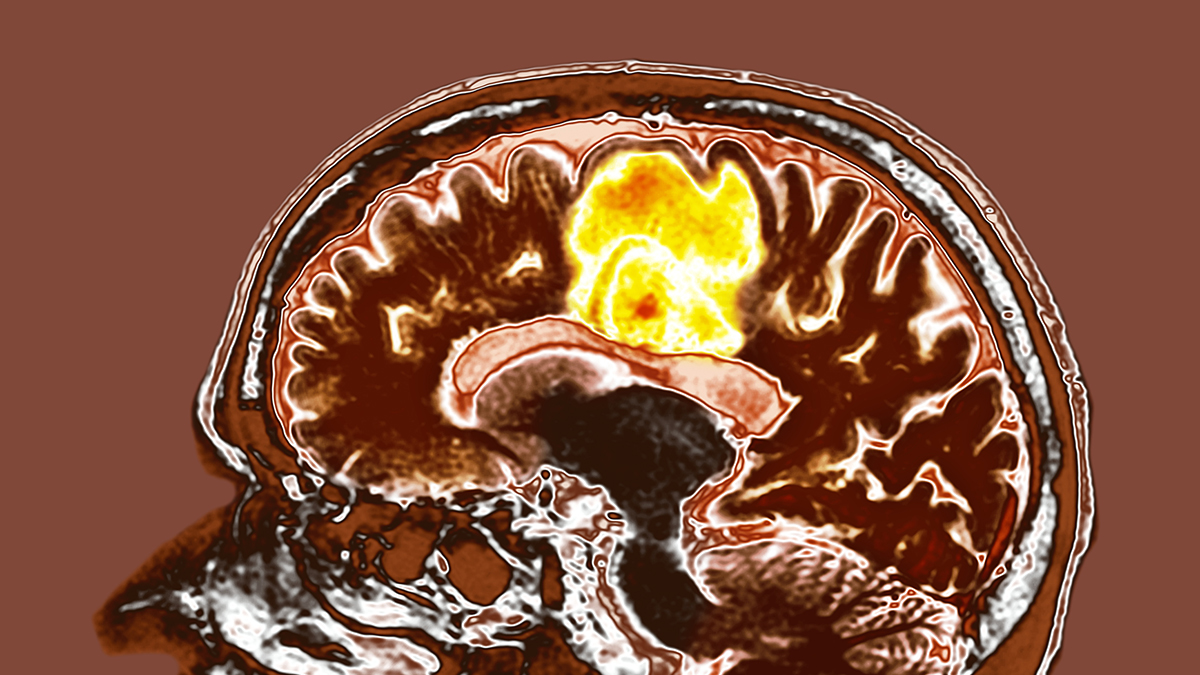

Glioblastoma is a particularly aggressive cancer, but encouraging results from a new study testing two common supplements on glioblastoma tumors could potentially lead to a new way to treat the disease.